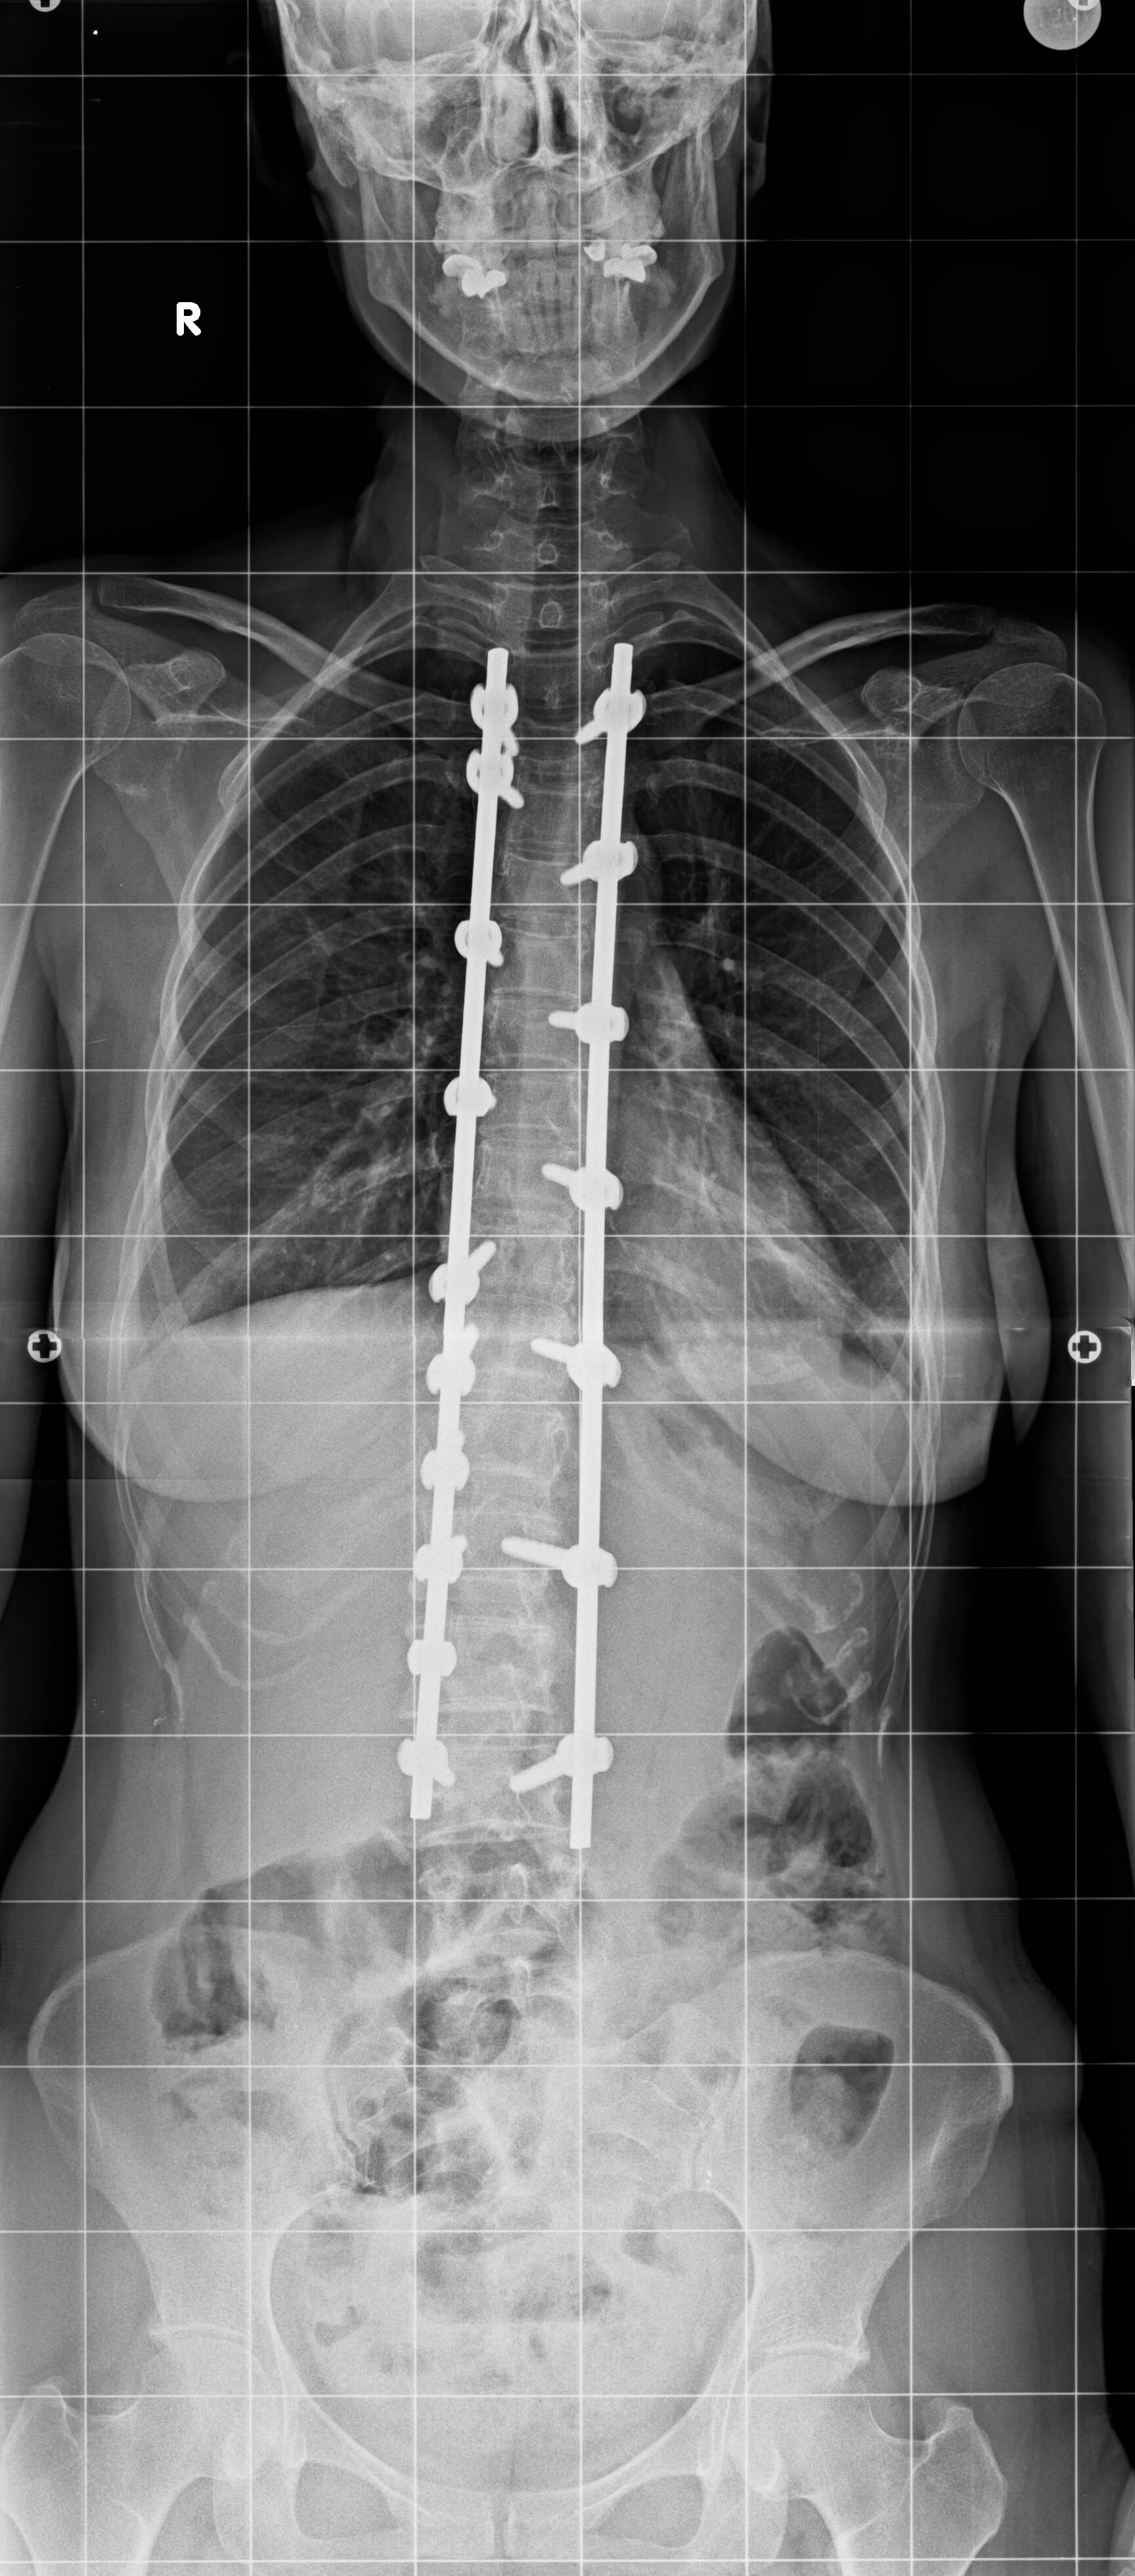

26 yaşında kadın hasta. Sırt ve bel ağrıları mevcut.

Ameliyat Sonrası